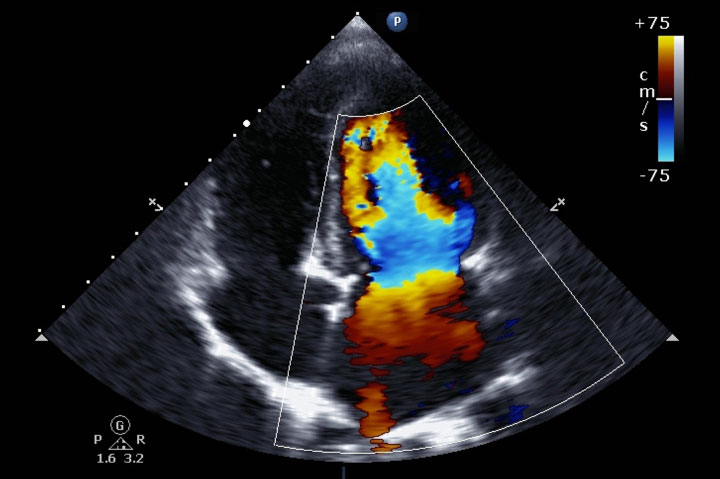

اکوکاردیوگرام آزمایشی است که برای نشان دادن نحوه عملکرد و دریچه های عضلات قلب از سونوگرافی استفاده می کند. امواج صوتی تصاویر متحرکی از قلب ایجاد می کنند تا پزشک بتواند دید خوبی نسبت به اندازه و شکل آن پیدا کند. ممکن است متوجه شوید که آنها آن را اختصاراً “اکو” بیان می کنند.

تغییرات امواج صوتی، که سیگنال های داپلر نامیده می شوند، می توانند جهت و سرعت حرکت خون در قلب را نشان دهند.